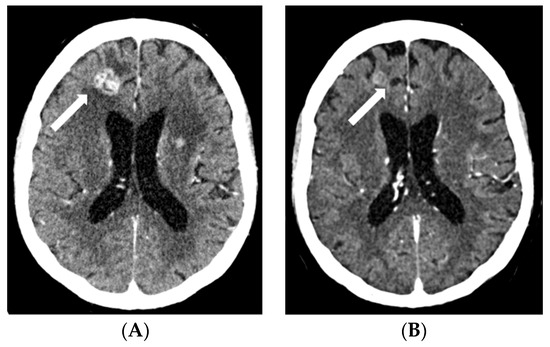

2.2. Case 2

2.3. Case 3